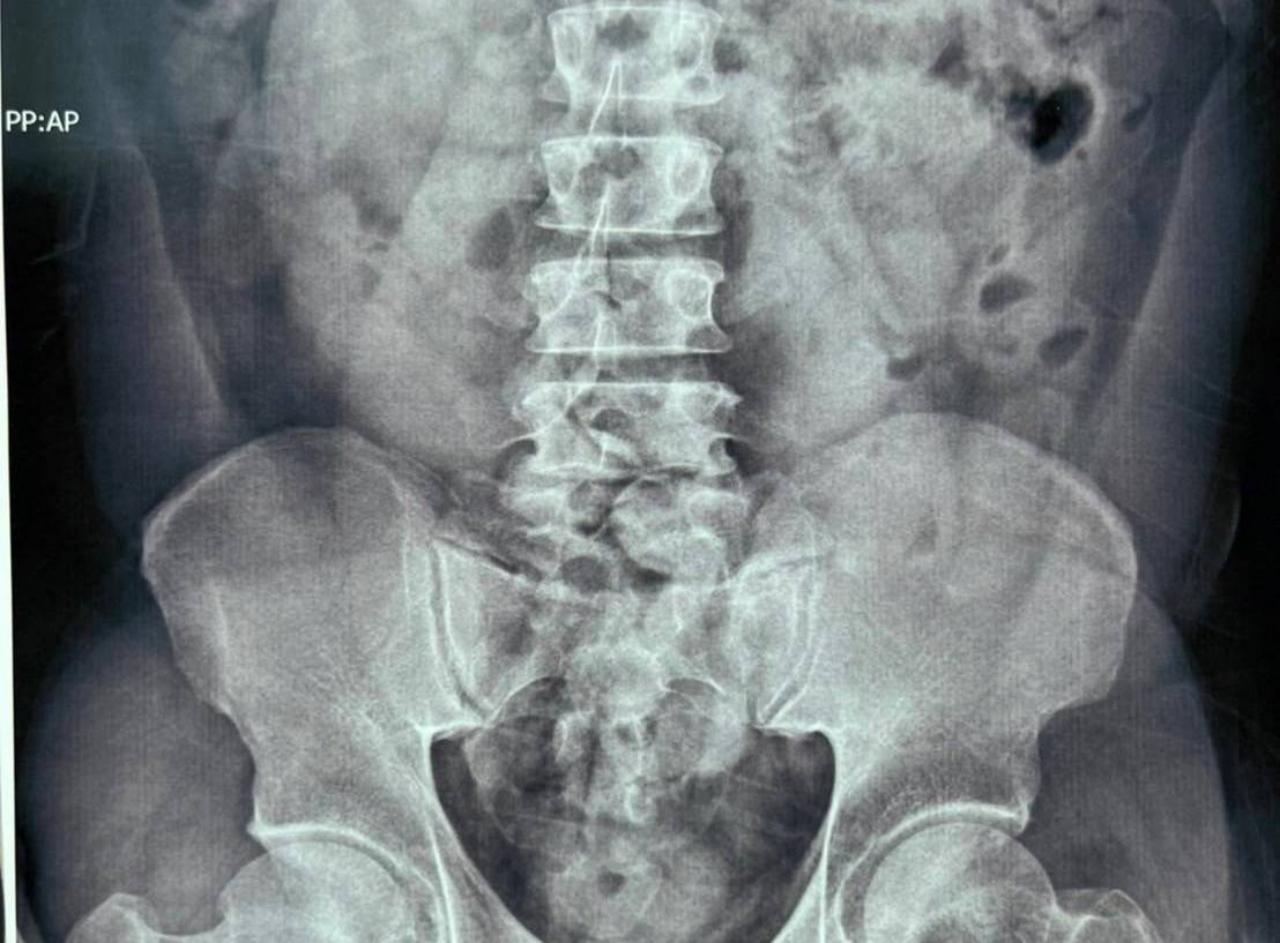

จากนั้นทำการหาข้อมูลเพิ่มเติมเกี่ยวกับที่พักของผู้ต้องสงสัยจนทราบว่าจะเข้าพักที่โรงแรมแห่งหนึ่ง โดยเจ้าหน้าที่กรมศุลกากรและเจ้าหน้าที่ชุดปฏิบัติการ AITF จึงจัดชุดสังเกตการณ์ด้านนอกโรงแรม กระทั่งวันที่ 6 มี.ค. 2565 เวลา 10.00 น. ชายชาวกินีรายดังกล่าวออกจากโรงแรมกักตัว เจ้าหน้าที่ได้เข้าตรวจค้นและนำตัวไปทำการเอกซเรย์ที่โรงพยาบาล ผลเอกซเรย์บ่งชี้ว่ามีสิ่งแปลกปลอมในช่องท้อง จึงนำตัวไปทำการขับถ่ายที่สำนักงานสุวรรณภูมิ เสร็จสิ้นเมื่อวันที่ 8 มี.ค. 2565

จากการตรวจสอบพบวัตถุแปลกปลอมเป็นยาเสพติดประเภทโคเคน จำนวน 54 ก้อน น้ำหนักรวม 1,080 กรัม มูลค่าประมาณ 3,240,000 บาท จึงแจ้งข้อหาให้ชายคนดังกล่าวทราบว่า การกระทำดังกล่าวเป็นความผิดฐานนำเข้ายาเสพติดให้โทษประเภท 2 และครอบครองยาเสพติดให้โทษประเภท 2 โดยไม่ได้รับอนุญาต ตามประมวลกฎหมายยาเสพติด และเป็นความผิดตามมาตรา 244 แห่งพระราชบัญญัติศุลกากร พ.ศ. 2560 จากนั้นนำผู้ต้องหาพร้อมของกลางส่งพนักงานสอบสวนดำเนินคดีต่อไป